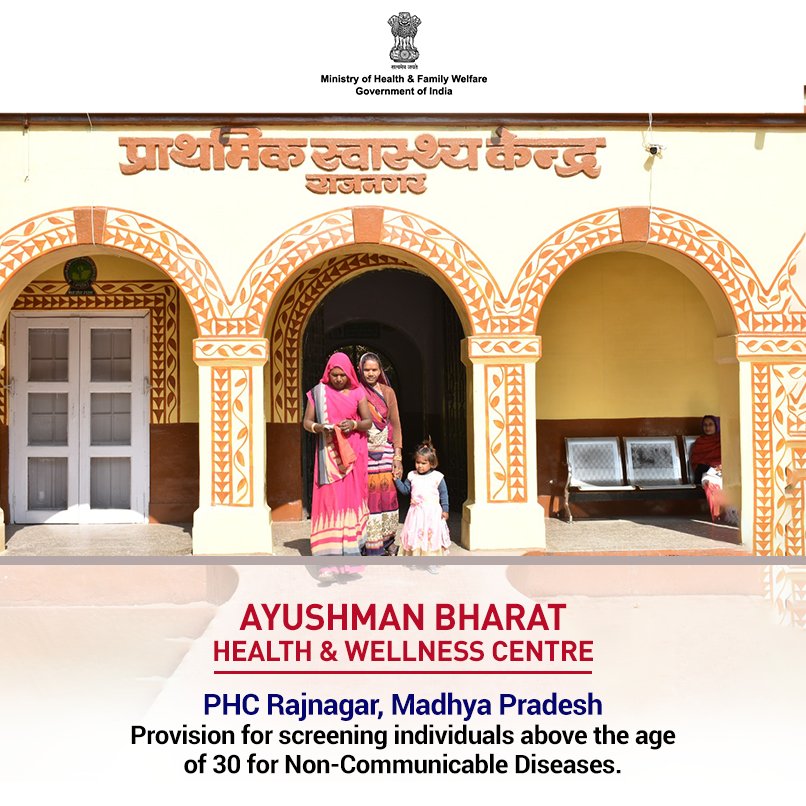

Health and Wellness Centres form a crucial pillar of

#AyushmanBharat, aiming to provide comprehensive primary health care. 4,503 HWCs have been operationalised across India.#SwasthaBharat#AyushmanBharatHWCpic.twitter.com/BuxRZqYDjC ಧನ್ಯವಾದಗಳು. Twitter ಇದನ್ನು ನಿಮ್ಮ ಕಾಲರೇಖೆಯನ್ನು ಉತ್ತಮಗೊಳಿಸಲು ಬಳಸುತ್ತದೆ. ರದ್ದುಗೊಳಿಸುರದ್ದುಗೊಳಿಸು